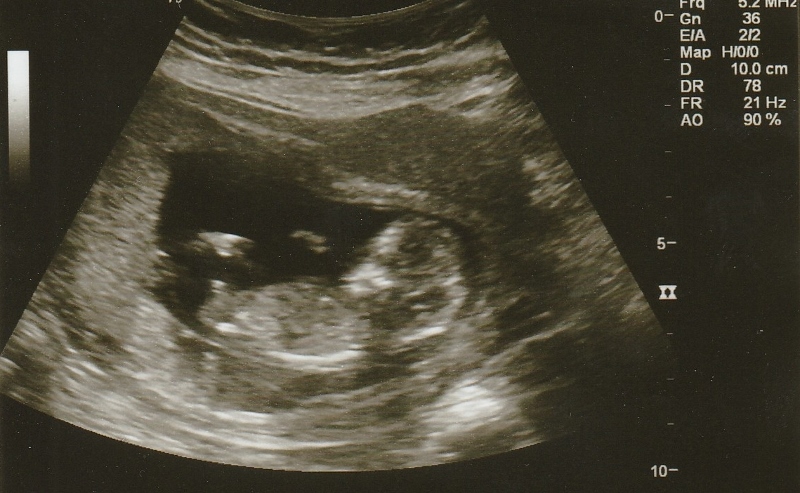

Hi! I had my first scan today at 12w3d and baby was measuring just a couple days ahead. Any guesses based on the nub? Thanks!! I am not sure that these all havve a clear nub but thought i'd add them just in case.

Attachment 22010Attachment 22009Attachment 22008Attachment 22007